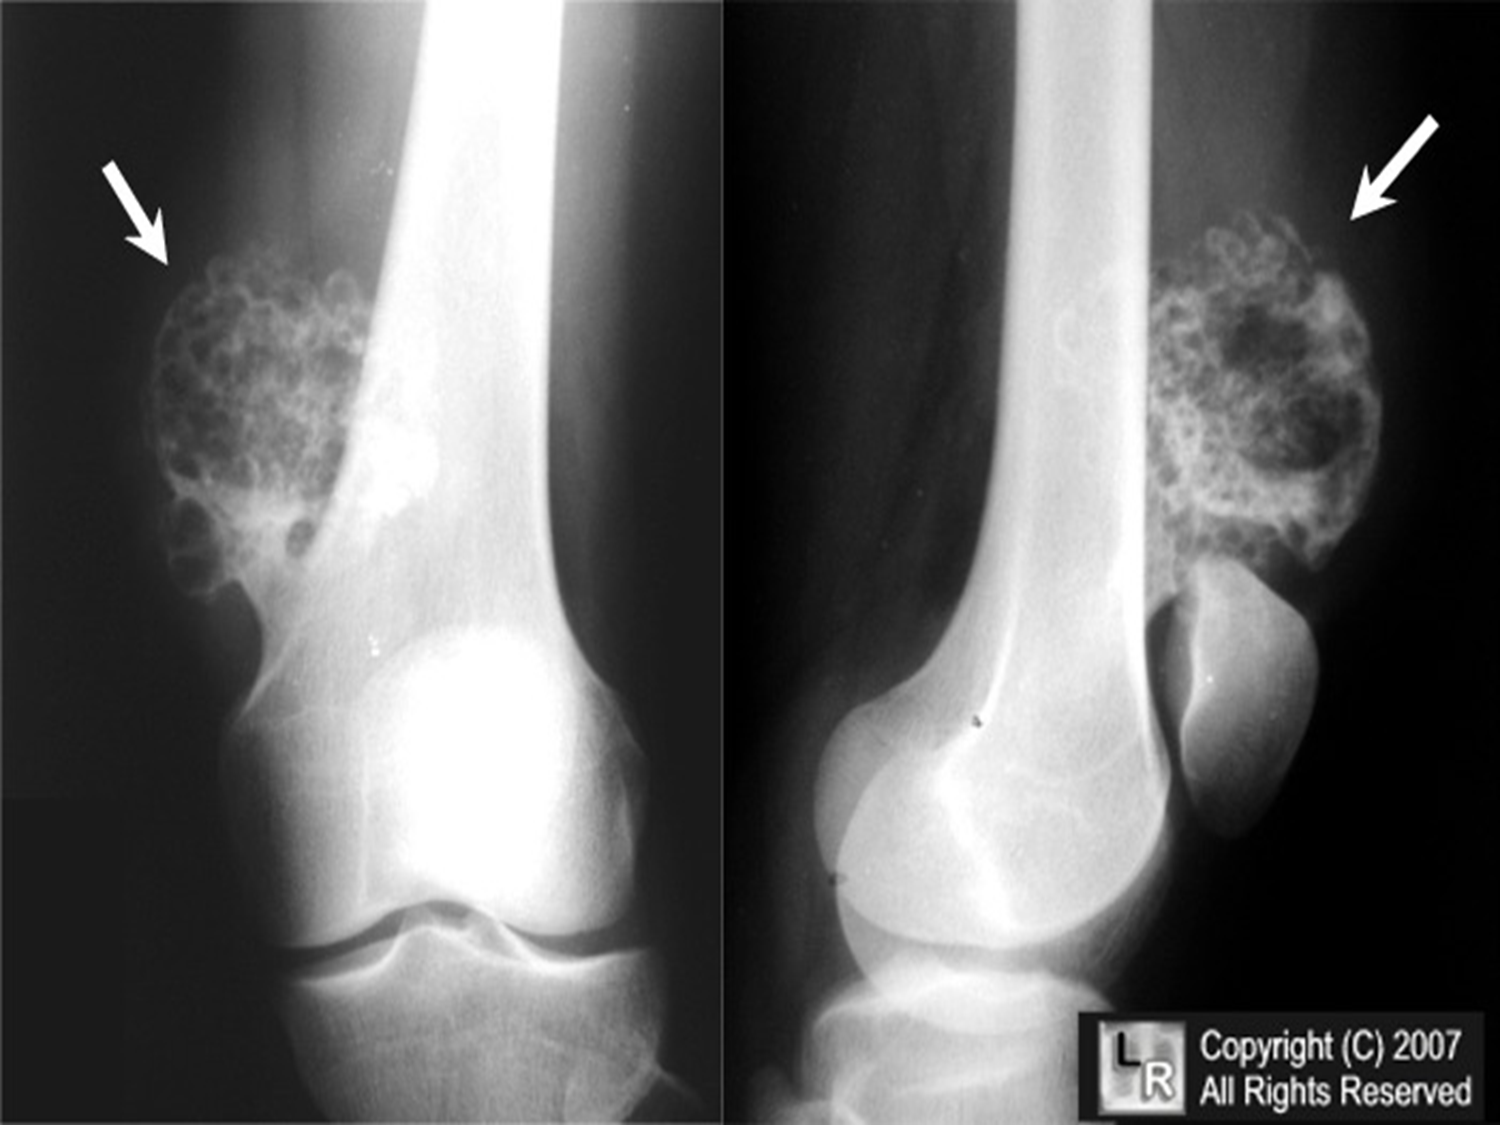

Osteochondroma

(Exostosis)

Benign projection of bone with a cartilaginous cap

Cause: idiopathic, hereditary

Complications: may turn malignant, pain, fracture of stalk

Radiographic Appearance: long axis of bone growth runs parallel to the parent bone and points away from nearest joint

Technical: No manual exposure factor change

Prognosis: Good, surgery only needed when there are mechanical

impingements